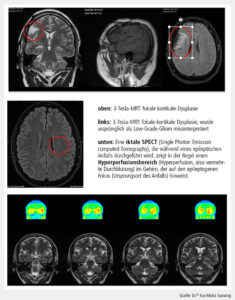

In der strukturellen Bildgebung hat die hochauflösende MRT (3 Tesla) die Computertomografie weitgehend ersetzt. Standardisierte Epilepsie-Protokolle, die dünnschichtige T1- und T2-Sequenzen sowie FLAIR-Sequenzen umfassen, erhöhen die Sensitivität zur Detektion von Läsionen wie Hippokampussklerosen, kortikale Dysplasien oder Tumoren. Dennoch bleibt bei etwa 20–30 % der Patient*innen die Bildgebung unauffällig, was die Herausforderung für die moderne Diagnostik verdeutlicht.

In den letzten Jahren hat die Bildgebung entscheidende Fortschritte erfahren. Insbesondere die Ultra-Hochfeld-MRT mit 7 Tesla eröffnet neue Möglichkeiten in der Detektion subtiler kortikaler Dysplasien oder Hippokampusveränderungen, die bei 3 Tesla unauffällig bleiben. Eine prospektive Studie konnte zeigen, dass bei Patient*innen mit MRT-negativer Epilepsie die 7T-MRT bei über 30 % bislang nicht erkannte Läsionen sichtbar machen konnte.

Abb. 2: Multimodale Bildgebung (MRT, SPECT)